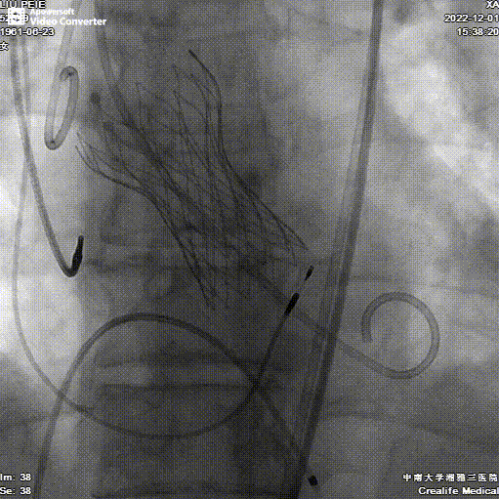

术前经过充分的CT评估,患者属于Type1型二叶式主动脉瓣,瓣叶增厚伴中重度钙化,左冠瓣叶钙化明显,R-N间可见钙化融合嵴,左室流出道呈稍敞口型。左右冠开口高度尚可,左右冠切线位瓣叶长度<冠脉开口到瓣叶附着缘距离。手术采用采用全麻+TTE的手术方式,以右侧股动脉为主入路,左侧股动脉为辅助入路。使用18mm球囊充分预扩,预装AV23瓣膜,瓣环上0-2mm定位释放,释放后多角度观察瓣膜释放形态及植入深度后,位置良好,冠脉血流灌注正常,微少量瓣周漏,跨瓣压差由术前的54mmHg降至术后的3mmHg。

手术没有“伤口”,心脏换了个瓣膜。整个手术时间持续仅仅不到一个小时,患者术后即刻感觉胸闷症状明显改善,术后12小时可以下床活动。经过张志辉教授团队的精心护理,患者术后第3天于12月4日康复出院。随着患者的顺利出院,标志着中南大学湘雅三医院心脏结构团队诊疗技术迈上新台阶。